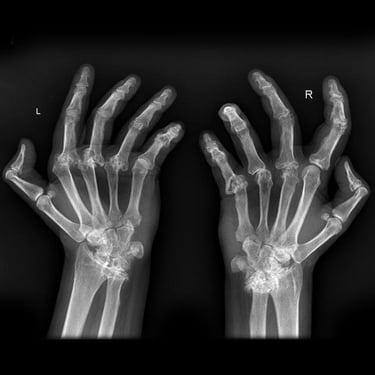

Sivam Hospital – Advanced Rheumatoid Arthritis Care in Chennai

At Sivam Hospital, we specialize in the diagnosis and management of rheumatoid arthritis (RA), providing expert care to reduce pain, control inflammation, and protect joint function. Our team of orthopedic specialists and rheumatology experts use advanced therapies and personalized treatment plans to help patients manage this chronic condition effectively.

We provide comprehensive care from early diagnosis to advanced treatment, making Sivam Hospital a trusted center for rheumatoid arthritis management. With state-of-the-art facilities, minimally invasive surgical options, and dedicated physiotherapy support, we help patients maintain mobility and improve their quality of life.

Expertise in Early Diagnosis & Comprehensive RA Management

Advanced Medical & Surgical Options for Joint Preservation

State-of-the-art Operation Theatres & Imaging Support

Personalized Pain Management & Rehabilitation Programs

Compassionate, Patient-focused Long-term Care

Live with less pain and more movement. Trust Sivam Hospital for expert rheumatoid arthritis care.